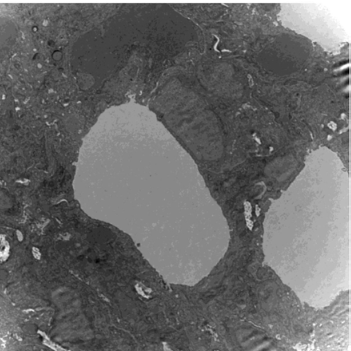

一种延缓皮肤衰老基因工程核酸因子膏的制备方法及使用方法